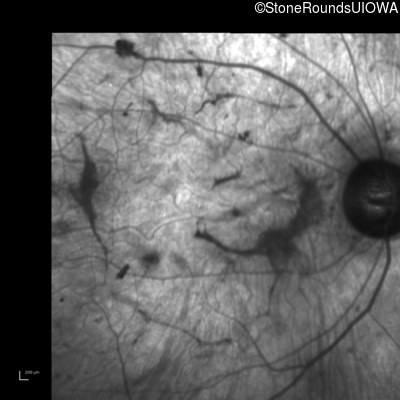

Age at visit: 38 years

This 38 year old woman had normal vision until age 22 when she noticed poor night vision when working as a camp counselor after college. Her hearing loss was first noticed at age 3 and was correctable with hearing aids.

Age at visit: 39 years

Age at visit: 41 years